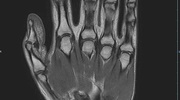

Gelenke

• Beurteilung von Knochen, Bändern und anderen Weichteilstrukturen der Gelenke nach Unfall.

• Arthrosediagnostik (Knorpelschaden)

• Impingement-Symptomatik

• Ursachenklärung bei wiederholter spontaner Gelenkluxation

• Ausbreitungsdiagnostik bei Gelenkentzündung, z.B. im Rahmen von rheumatischen Grunderkrankungen